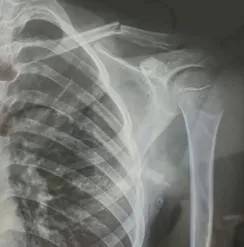

皇冠信用网代理登3(www.hgty.us)为您提供皇冠登录,皇冠盘代理、会员皇冠信用网代理开户、皇冠会员开户业务 10月23日,内蒙古赤峰市宁城县苏木皋小学一学生被老师打伤致锁骨骨折皇冠信用盘结算日是哪天。10月31日,家长贾女士给生活报记者打来电话称,事件已经过去一周时间了,但是校方还没有到医院给孩子道歉,且涉事教师还在上班。

10月30日,内蒙古自治区赤峰市宁城县苏木皋小学一学生家长贾女士给记者打来电话,介绍了孩子被打的原因皇冠信用盘结算日是哪天。贾女士称,放学通道的墙上有一个电灯的开关,好多孩子放学时都随手去拨弄开关。出于安全考虑,学校和老师都禁止孩子拨弄开关。23日放学时,他儿子和另一个同学调皮,再去拨弄了那个开关,被正在值班的另一个班的班主任发现,把她儿子打了,且打骨折了。

图片由报料者提供